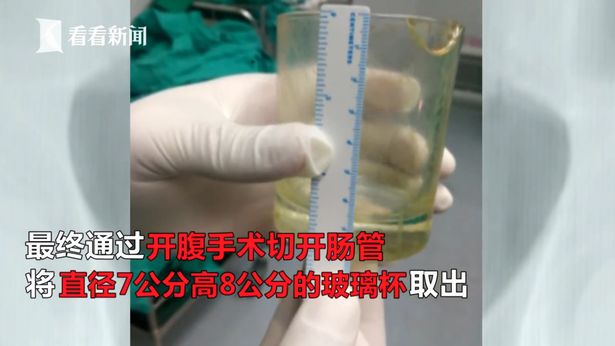

最後在雙方溝通後,決定進行開腹手術來取出玻璃杯,才終於解決男子「忍受了2天」的痛苦,但當時醫生詢問玻璃杯是怎麼進去的時候,男子不願做任何回答。此外醫生也說,通常在直腸會出現異物70%是為了尋求「性刺激」,如果異物真的不小心滑入體內無法自行取出,一定要趕快就醫,不要因為害羞而傷了自己。